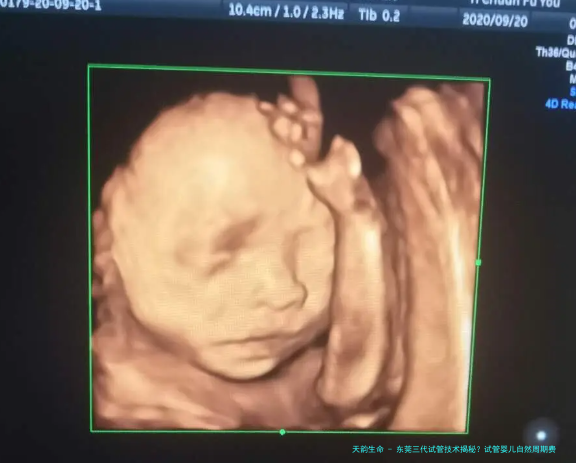

这项技术是在试验室中将精子和卵子结合造成受精卵,并培养成胚胎。当胚胎发育到必须阶段(通常是第5天或第六日的囊胚期),胚胎学家会提取少量细胞体进行基因检测。这种被称为胚胎植入前遗传生物学检测(PGT)的技术,能够检查筛选胚胎是否携带特定的染色体异常或导致疾病基因,进而选择优质的胚胎进行移植。